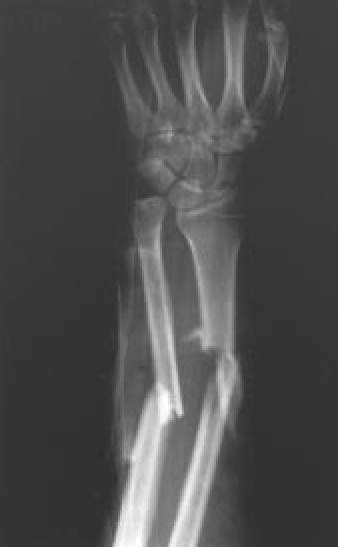

Fig. 4A.: Fractura diafisaria de cúbito y radio. Proyección anteroposterior